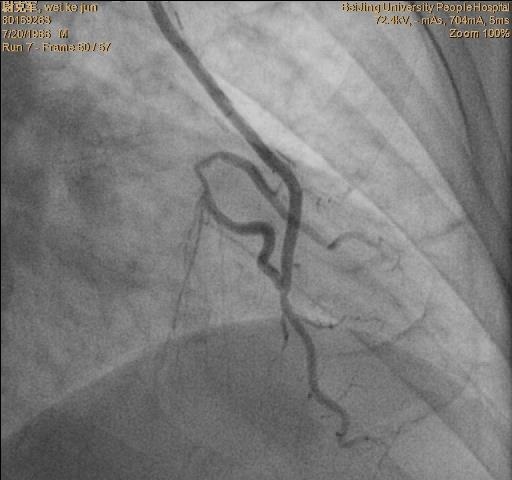

冠脉造影提示:双支病变。 见下图:

•术后一周复查造影,了解LIMA桥的状况,同时行RCA 和D的介入治疗。见下图: